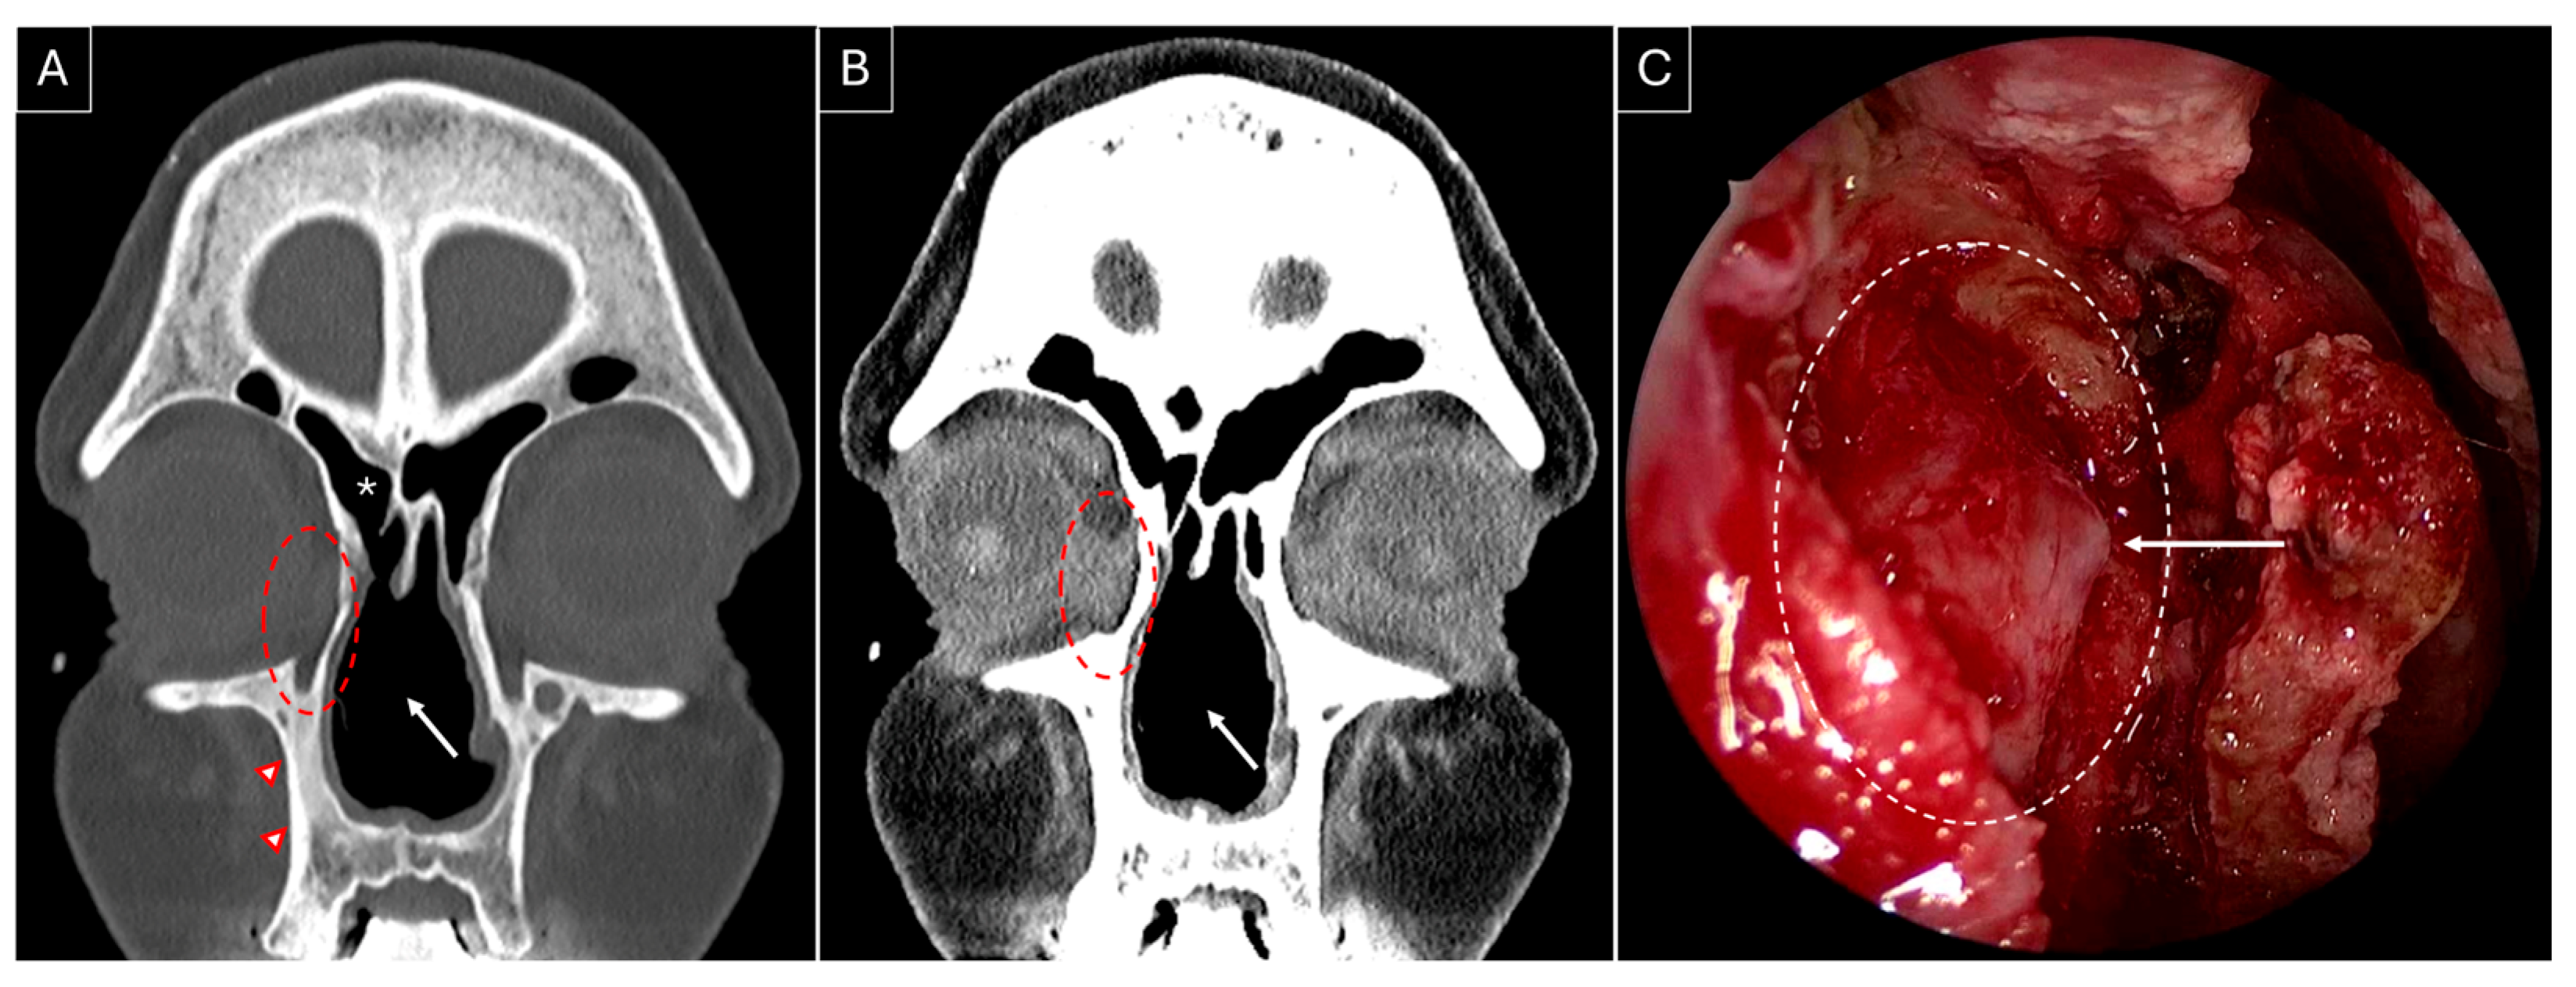

3.3. Our Experience: Two Patients of GPA Who Underwent Endoscopic DCR